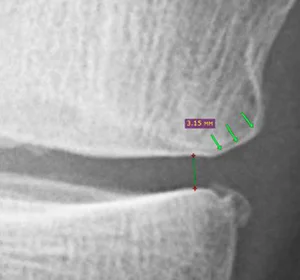

При цьому на рентгені можна побачити відновлення краєвої зони хряща (позначено стрілками).